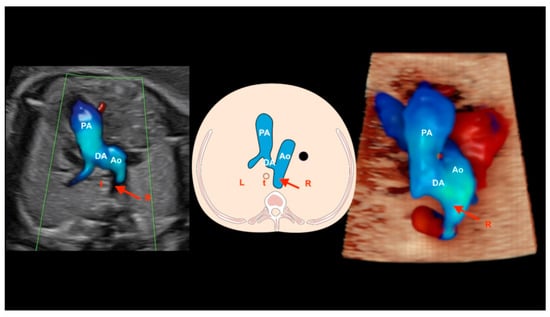

12. Right Aortic Arch

When the aortic arch is in an abnormal position, such as a right arch, the left subclavian artery has a retroesophageal/retrotracheal course that may cause the compression of the esophagus and/or trachea (vascular ring). A U-shaped image allows the diagnosis of this anomaly in the three-vessels view (Figure 26). The double arch of the aorta is the only form of vascular ring in which the vascular ring consists entirely of vessels. In a double arch, the right arch is usually larger than the left arch. The two aortic arches, the pulmonary trunk, and the ductus arteriosus form the vascular ring in the shape of a trident [58].

Figure 26.

Right aortic arch. Note that the aortic arch is located to the right of the trachea (red arrows). A schematic drawing of the three-vessels and trachea view is shown in the center, an ultrasound image with HDlive Flow is shown on the right, and HDlive Silhouette is shown on the left. PA: pulmonary artery; Ao: aorta; t: trachea; DA: ductus arteriosus; R: right side; L: left side.